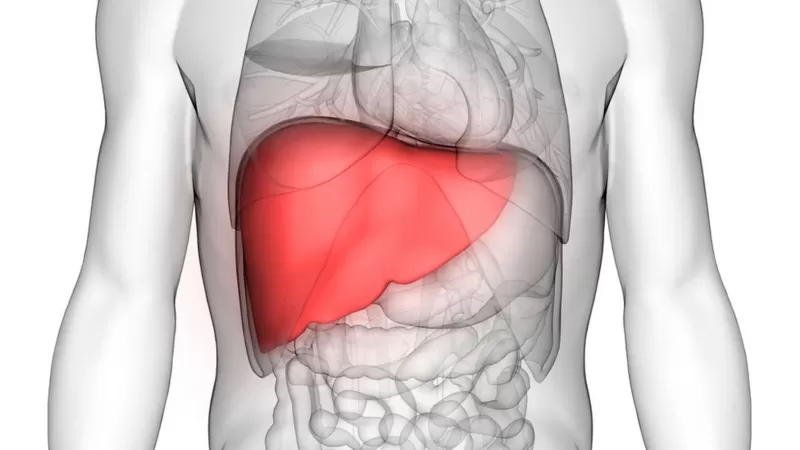

Experimentos com animais revelaram uma notável capacidade da bactéria de estimular o crescimento saudável de tecidos do corpo — uma “alquimia biológica” que levou, por exemplo, o tamanho do fígado a quase dobrar. Pesquisadores também já observaram que este micróbio consegue converter um tipo de tecido em outro.

Os experimentos, realizados nos Estados Unidos, mostraram que a infecção se dirigia para o fígado dos animais, onde a bactéria fazia um sequestro controlado do órgão — reprogramando-o para interesse próprio.

Os resultados, publicados na revista científica Cell Reports Medicine, mostraram que o fígado dos tatus quase dobrou de tamanho.

Era esperado que o crescimento pudesse ser defeituoso ou até canceroso, mas uma análise detalhada mostrou que foi um processo saudável e funcional, incluindo um conjunto normal de vasos sanguíneos e dutos biliares.

Parece que a bactéria que causa a hanseníase rebobina o relógio do desenvolvimento do fígado.

As células hepáticas totalmente desenvolvidas são potências metabólicas com centenas de funções no corpo.

Mas as bactérias Mycobacterium leprae conseguem levar as células de volta a um estágio anterior — como se voltassem à adolescência — em que podem aumentar rapidamente em número, antes de amadurecer e voltar à idade adulta.

Observando a atividade de diferentes partes do DNA, os cientistas observaram um comportamento mais próximo ao de um animal muito mais jovem ou mesmo de um feto, quando o fígado ainda está se formando.